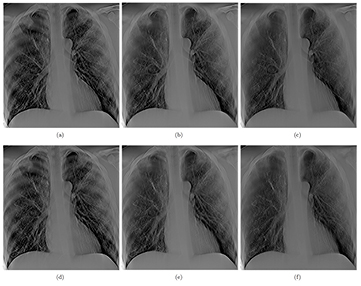

Projection images of the anthropomorphic chest phantom were acquired and reconstructed using RTT for image quality assessments. Tomosynthesis images with the same imaging dose but different angular spans were reconstructed and compared. Three datasets, each acquired using 29 projections at 110 cm SID and 80 kVp and 0.6 mAs per projection, were captured with angular spans of 11.6°, 23° and 34°. For each projection, 0.6 mAs results in approximately 62.3 µGy incident air kerma per projection view at the patient entrance plane, which is 25 cm in front of the detector. The dose per projection is more than sufficient for the typical dose of projection view reported in clinical DCT systems (Dobbins et al 2008, Sabol 2009). Three tomosynthesis slices from these datasets, focused at the same plane, are shown in figures 12(a)–(c), respectively. Tomosynthesis slices from all three configurations at another depth are shown in figures 12(d)–(f) as well. All reconstructed images clearly show the airways and detailed pulmonary vascular structures in the physical phantom. As the angular coverage increases, the artifacts from out-of-focus objects are reduced. At 11.6° angular span, ribs out of the focal plane can be seen in the slice, while at 23° and 34°, the visibility of these out-of-focus ribs is reduced. This is due to the improved in-depth resolution from increased angular span, as shown in the ASF measurement above. However, as the angular coverage increases, the angular step between projection images increases as well, resulting in ripple artifacts due to under sampling of the angular range (Deller et al 2007, Machida et al 2010). These ripple artifacts are caused by the high contrast objects (i.e. ribs) far outside the imaging plane that are not sufficiently blurred.

Figure 12. (a) and (d) show two slices at different depth (separate by 2.4 cm) reconstructed from 29 projection images acquired over 11.6°, (b) and (e), and (c) and (f) show the same slices reconstructed with same number of projection images but with 23° and 34° angular coverage, respectively. All three sets of images were acquired at the same total dose. It can be seen that the wider the angular coverage the lesser is the out of plan tomo artifact (such as those from the rib cage), due to improved in-depth resolution.